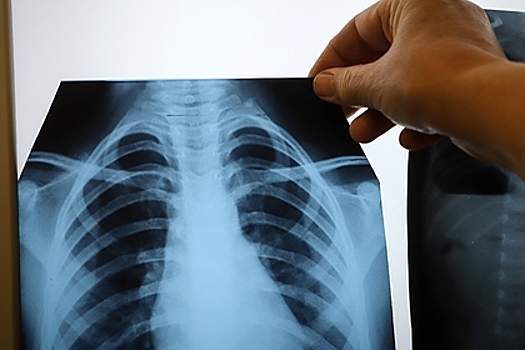

Он считает, что по легким человека наносится «первый и серьезный удар», так как в них — множество рецепторов, к которым, спускаясь по дыхательным путям, прикрепляется вирус.